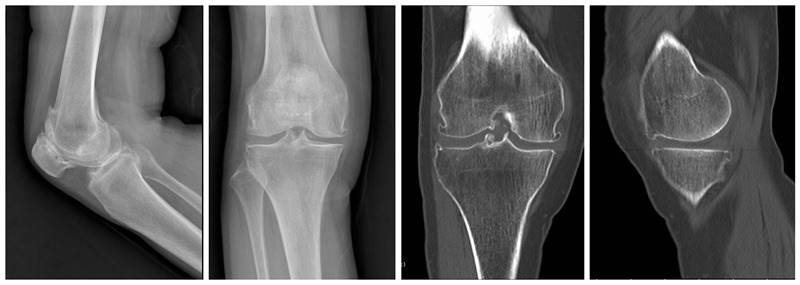

内侧单髁置换术(非骨水泥型)

术前

术后检查

膝关节单髁置换术后的翻修率的一个主要原因是无菌性假体松动。临床上常常用术后X线平片上是否出现透亮带来判定假体是否松动。事实上部分骨水泥型单髁假体,术后x线片常常可见生理性透亮带,容易误诊为假体松动,从而导致不必要的术后翻修,生物型单髁置换假体的推广减少了单髁翻修率,延长了假体的使用寿命。

现阶段生物型单髁假体也逐步被越来越多医生与患者选择。对于生物型假体,需要注意以下几点:(1)垂直截骨开槽避免用常规骨水泥型假体工具,以免开槽过宽导致假体置入松动。(2)开槽过程中需要特别谨慎小心,敲击力度适宜,以防胫骨劈裂骨折。(3)年龄大,骨质疏松明显以及股骨髁坏死病例用生物型假体应更加慎重。